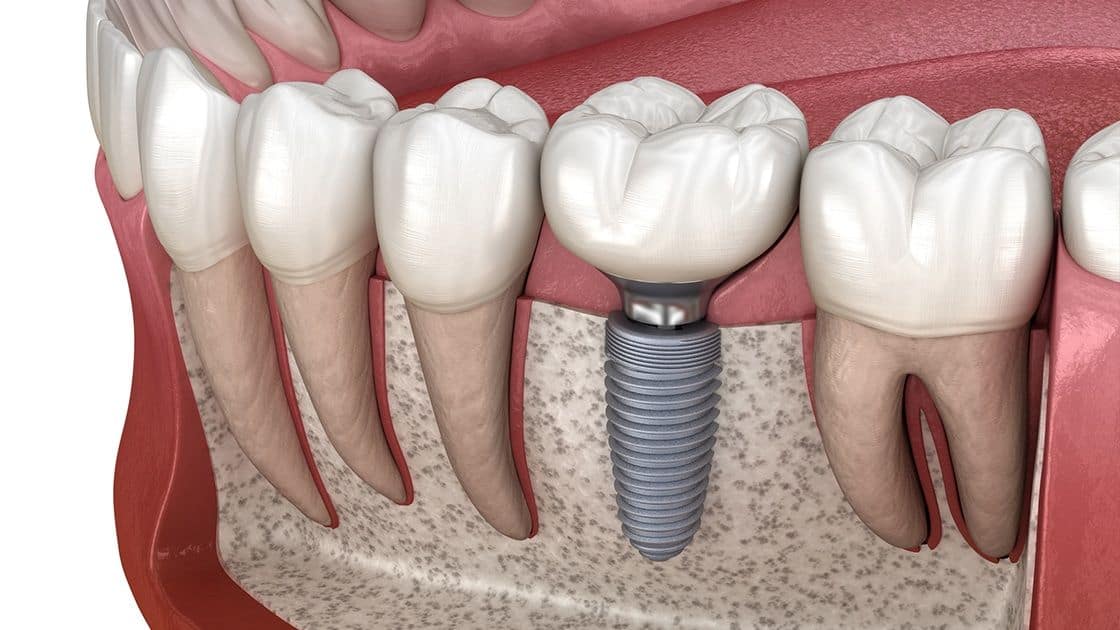

Imagine driving at night in the rain without a GPS navigation system. It would be challenging, right? The mouth is a similar environment: dark and moist. At Finesse Dental Implant Center, we use a guided surgery system to ensure precise implant placement.